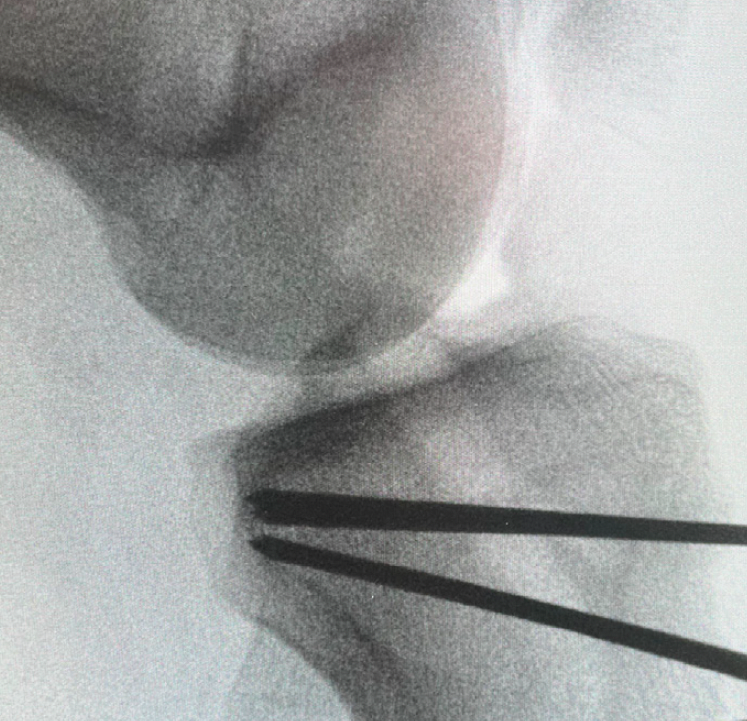

The first key step is to identify the insertion of the patellar tendon over the ATT. Then, the fascia lata and tibialis anterior muscle are released following the Keblish lateral approach. The deep medial collateral ligament is released medially. It is then possible to position double-curved retractors on both sides of the tibial metaphysis. Two proximal K-wires (diameter 2.5mm) are inserted at the patellar tendon insertion, positioned 1 cm away on both sides. Next, the two distal K-wires are inserted as planned pre-operatively, with the goal being to achieve a final tibial slope of 4-6° [7] Dan MJ, Cance N, Pineda T, Demey G, Dejour DH. 4-6 degrees is the Target Posterior Tibial Slope post Tibial Deflection Osteotomy according to the Knee Static Anterior Tibial Translation. Arthroscopy. 2023 Jul 19; . The wires must converge at the posterior cortex, 1 cm below the tibial plateau (Figure 6). The osteotomy is performed using an oscillating saw, using the proximal wires as guides inferiorly and the distal wires superiorly. In order to weaken the hinge without entirely breaking it apart, it is best to gently butt up against the posterior cortex, as if “knocking on the door”. The biplanar osteotomy is then performed just behind the patellar tendon. The bone wedge can be removed. The hinge is tested by lowering the proximal part over the distal part. Reduction is applied by gently extending the lower limb. A staple 2 cm lateral to the patellar tendon is used for temporary fixation, and the slope is checked using fluoroscopy. If the result is satisfactory, it is also fixed medially with a staple. Once the osteotomy is reduced, the tibial tunnel will be slightly angulated and it will need to be drilled again. This is done by pushing the drill bit by hand to avoid applying excessive stress on the osteotomy line. The graft can then be passed through and fixed in place. Fixation is performed in 70° of flexion to avoid any genu recurvatum.